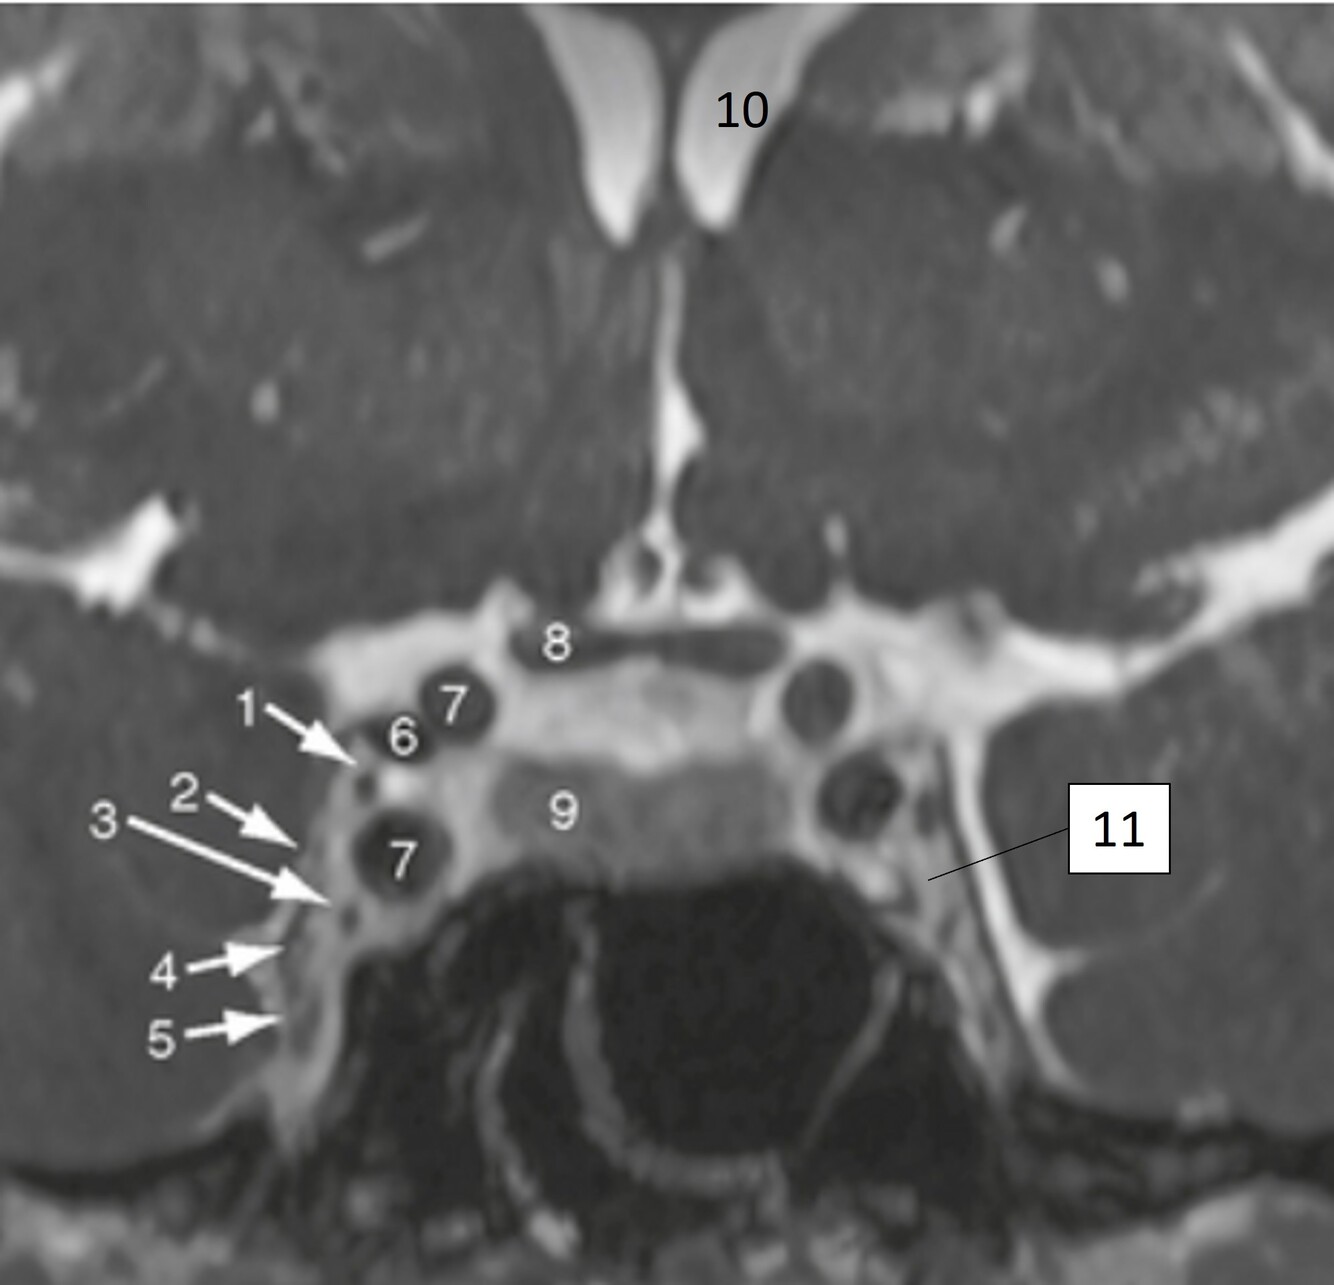

Label 1-3

1-Lt Optic nerve

2-Optic chiasm

3-Rt Optic tract

Label 1,10,12

1=Lt cerebral peduncle (midbrain)

10=Interpeduncular cistern

12=Cerebral aqueduct

Label 7-11

7=Rt Internal carotid artery

8=Optic chiasm

9=Pituitary gland

10-Lt lateral ventricle

11=Lt Cavernous sinus